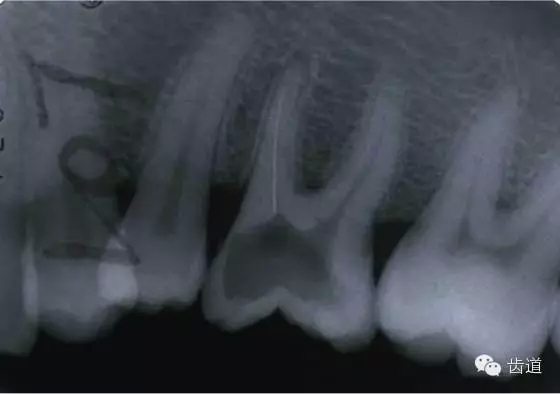

五、下唇麻木

(一)發(fā)生原因:主要由下齒槽神經(jīng)損傷所致

1.治療操作中藥物、器械或根充物超出根尖孔,進(jìn)入下頜管損傷下齒槽神經(jīng)

2.解剖因素:下頜牙齒根尖距下頜管太近,有些牙根與下頜管相連,以下頜第二恒磨牙多見(jiàn)

左下7根充后下唇麻木

左下5根管預(yù)備后下唇麻木